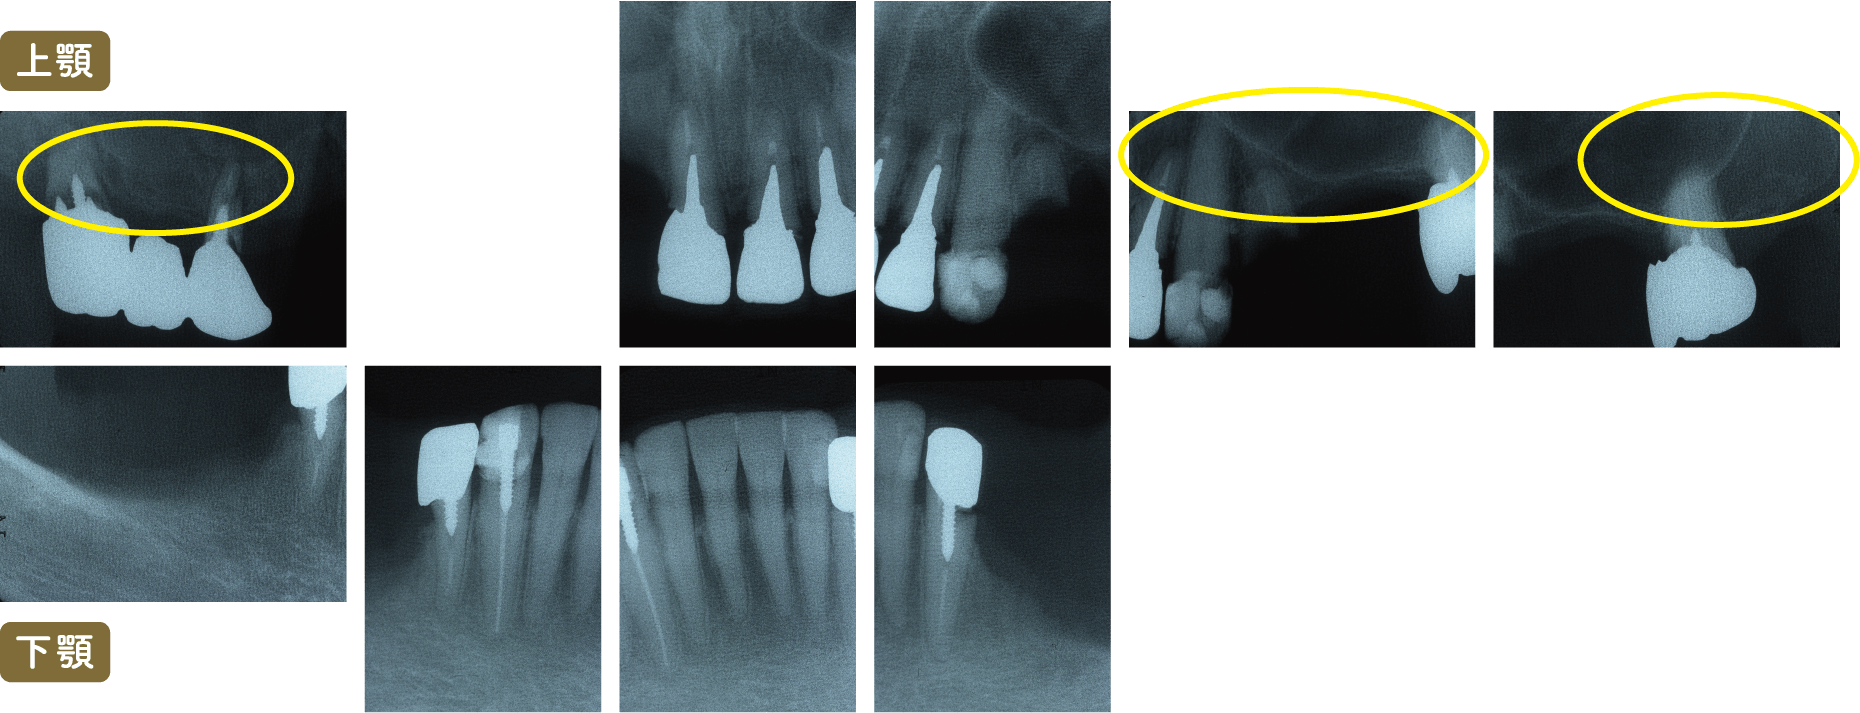

■術後レントゲン写真

は再根管治療を行いました

根の先まで根管充填されている事がわかると思います

根管充填はMTAを使用しています

この症例では

残存している歯(15本)全ての治療が必要でした。

上顎では左上3以外すべての歯に根管治療を行いました。

左上7にはソフトアタッチメント、左上4・右上5,7にはコーピング(歯に装着する金属のキャップ)、左上1,2,3・右上1にはレスト(義歯の沈下を防ぐための維持装置)を用いてスマートデンチャーを作成。

下顎では左下3・右下3,4に根管治療を行い、その後にソフトアタッチメント

左下1,2・右下1,2には虫歯の処置後CR充填を行い、その後左下1,2にはレストを用いてスマートデンチャーを作成。